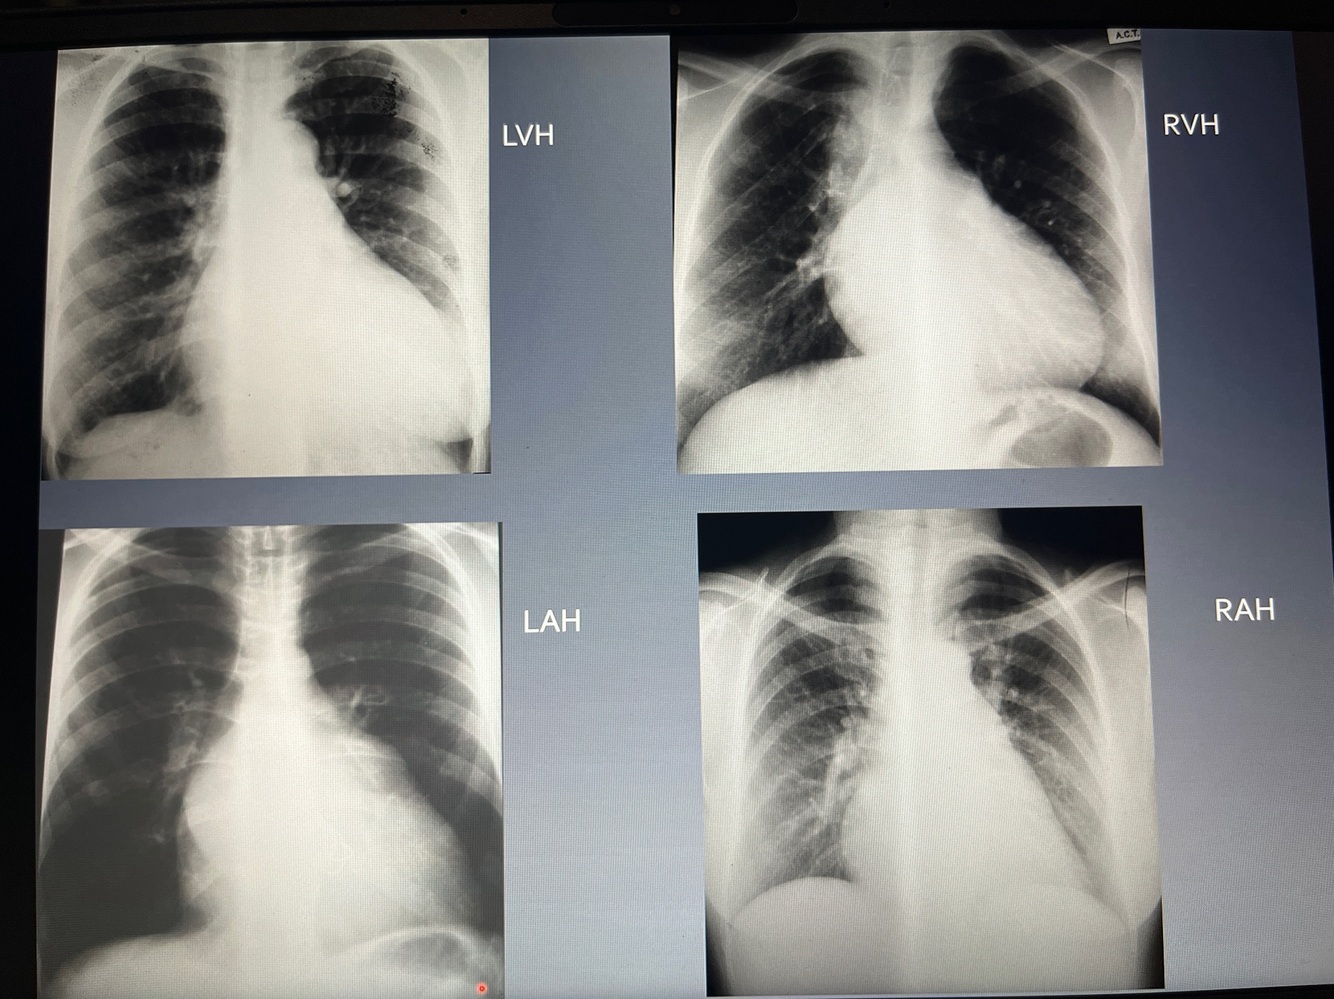

Patterns of lobar collapse

LVH-apex move up and down

RVH-apex up and out

LAH-double density behind the heart

RAH-bulge at right heart boarder